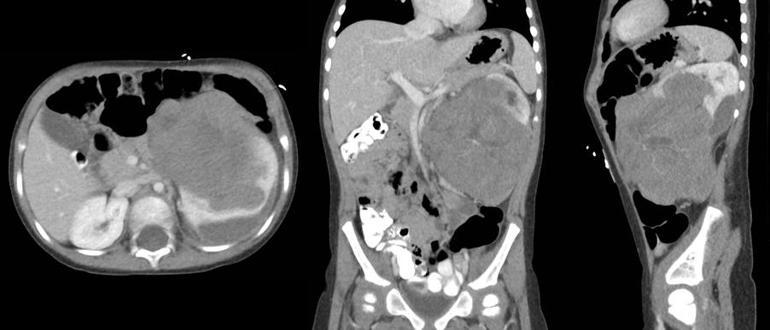

Kocaman, tanı sürecinde ultrasonografi, MR ve BT gibi görüntüleme yöntemlerinin kullanıldığını, ayrıca idrarda ölçülen belirli maddelerin nöroblastom açısından önemli ipuçları verdiğini ifade ediyor:

Wilms tümörünün genellikle 3–4 yaş civarında ortaya çıktığını söyleyen uzman doktor, çoğu vakanın ebeveynlerin karında fark ettiği kitleyle hastaneye başvurduğunu anlatıyor:

“Karında şişlik, kanlı idrar, yüksek tansiyon ve iştahsızlık en bilinen belirtiler. Bazı çocuklarda uzun süre hiçbir belirti vermeden büyüyebiliyor. Bu nedenle karında ele gelen herhangi bir kitle mutlaka değerlendirilmelidir.”

Tanıda ilk adımın ultrason olduğunu belirtmesinin ardından MR, BT ve kan tahlillerinin uygulandığını, kesin tanının yine patolojik inceleme ile konduğunu vurguluyor.